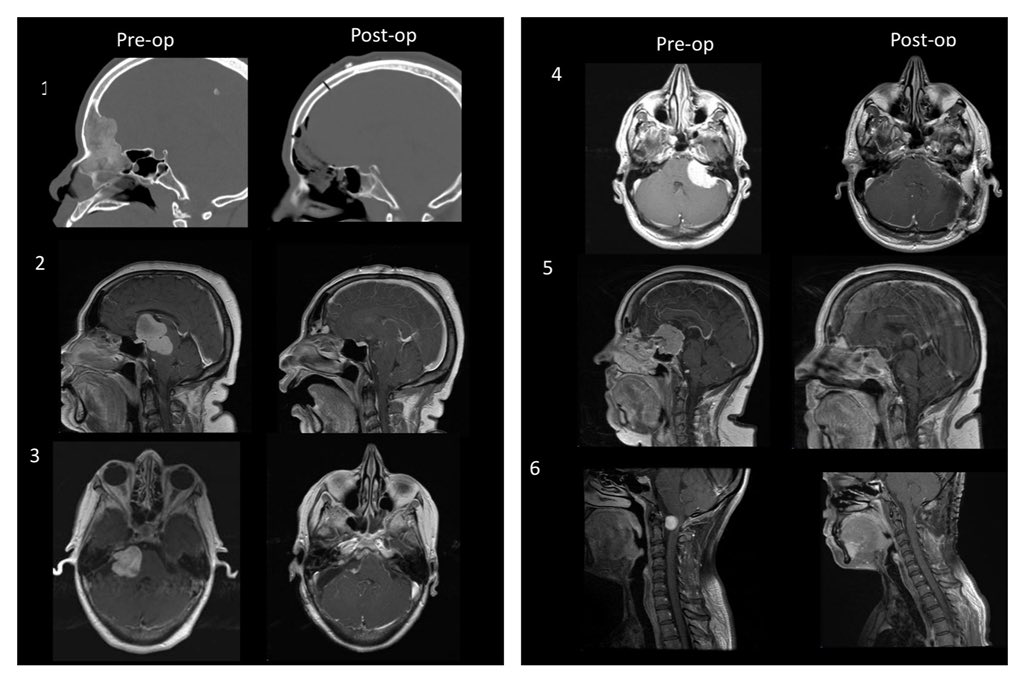

As I look back on #2019 I am grateful to be able to work with such an amazing team of

#surgeons,#nurses,#residents,#medicalstudents, and staff. Happy to say these last 6 patients operated on in 2019 are doing well

Looking forward to helping this population in #2020 #nsgypic.twitter.com/t8tl1EHXhj